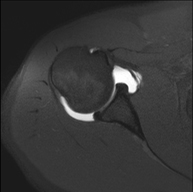

- RM Hombro

Exploración para el estudio de lesiones en tendones, músculos y articulación. Su principal utilidad reside en diagnosticar las lesiones de los tendones del manguito rotador. Tiene una duración aproximada de 20 minutos. No emplea radiación ionizante.

- Artro-RM Hombro

Exploración para el estudio de las lesiones en pequeñas estructuras anatómicas de la articulación que suelen lesionarse en pacientes que sufren luxación o inestabilidad crónica. El estudio viene precedido por una inyección de contraste en el interior de la articulación, realizada bajo control de rayos X. La duración global de los dos procedimientos es de 50 minutos.